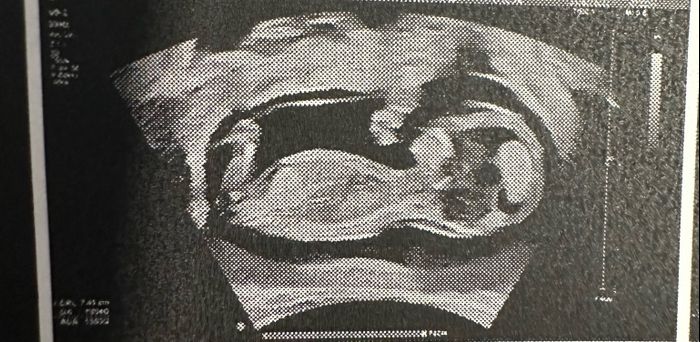

Ciao ragazze! Nell'attesa chi vuole giocare con me? Secondo voi è maschio o femmina? Fatta eco stamattina a 11+6! Io onestamente non saprei dire☺ ho letto la teoria Nub theory ma non riesco a interpretare la mia eco!